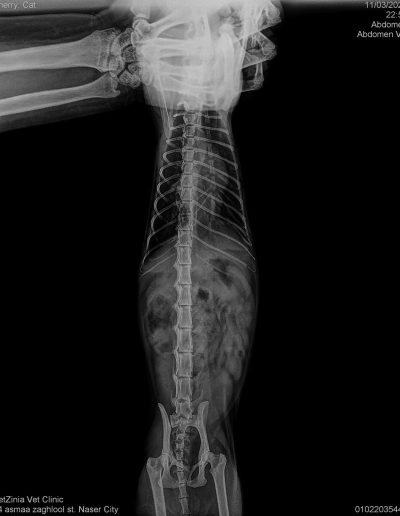

Taxi 6 months, Hit by a car and had a leg Amputation. Stayed more than 8 months at vet and then went to our kahu shelter to get his vaccines and the care need it